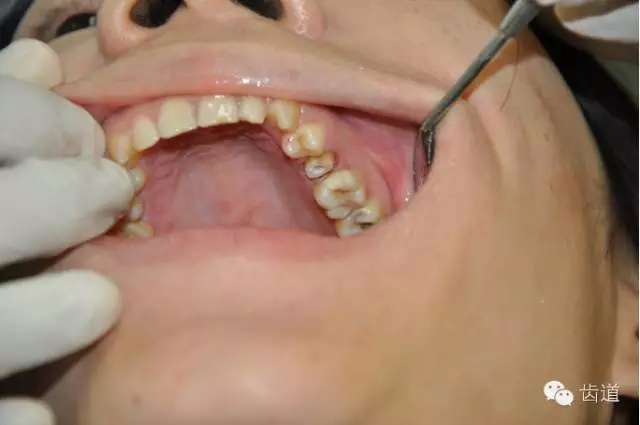

在口腔修復(fù)中,對于需要做全冠的牙齒要進(jìn)行牙體預(yù)備,靠近牙齦的地方所均勻磨出的一圈平臺稱肩臺。

如果肩臺制備不到位或不制備肩臺,全冠戴入后冠邊緣就會形成異物懸突,刺激牙齦,引起齦發(fā)炎出血,時間一長甚至?xí)?dǎo)致牙冠腐爛。

2.如果印模齦緣處不清晰,技工將很難掌握肩臺的位置,最終修復(fù)將有可能出現(xiàn)內(nèi)冠邊緣懸突和肩臺懸突的問題。

內(nèi)冠邊緣懸突是導(dǎo)致牙齦變色的"罪魁禍?zhǔn)?quot;

肩臺懸突易出現(xiàn)繼發(fā)齲